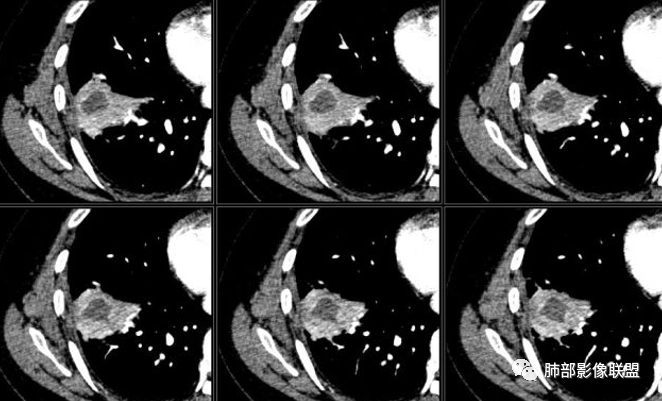

南边:今天的病例肺内部分基本都是炎性特点,问题就在于胸膜。

糊墙:肺内病灶不侵犯壁层胸膜或以外,与壁层胸膜相对而言分界清楚。

栽赃:病灶侵入壁层胸膜及胸膜外脂肪间隙、胸壁其他结构等,相对在病灶中央区域,与胸膜分界不清。

南边:看肺内病灶与胸膜分界清,增强后强化不一致,需要综合分析。

这是糊墙。

这就栽赃。都突到外面去了。

看看这个,骨头都侵袭了。

南边:一般这类侵袭,是中央地带毛刷状延伸到胸膜内。

我只是邓较瘦:南大这个我感觉局部似乎是栽赃呢 箭头那里是啥?

南边:栽赃是这样过去的,中间不会脂肪间隙清晰。

胸壁的组织,除非你怀疑胸壁转移结节。

转移淋巴结。

局部侵犯。有差异。

我只是邓较瘦:这个是侵犯出去不是淋巴结吧?

南边:不是,你看看强化与淋巴结不一致。

我只是邓较瘦:强化与肿瘤差不多。

南边:是。